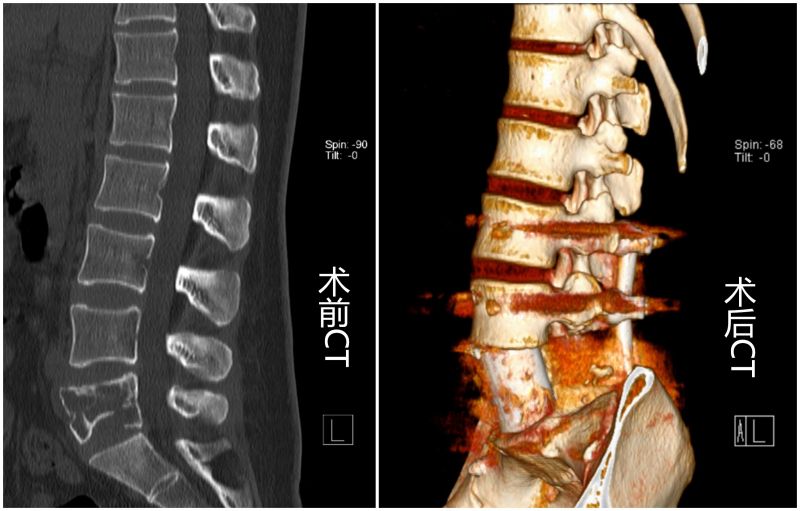

34岁缪女士4天前因不慎扭伤腰后出现腰痛伴右下肢麻木,以为患上了腰椎间盘突出症,在当地医院行腰椎磁共振,发现腰5椎体骨质破坏,初步考虑脊柱肿瘤,这对缪女士及家人而言犹如晴天霹雳。经多方打听,缪女士及家人慕名到闽东医院脊柱外科主任医师刘成招处就诊。入院后,刘成招结合患者病情初步考虑脊柱骨巨细胞瘤,但肿瘤较大,侵蚀大部分椎体,并造成了神经根压迫,具有明确手术指征。术前联合血管介入外科、麻醉科、医学影像科、病理科等相关学科进行多学科会诊,并与上海市第九人民医院赵杰教授团队专家进行线上讨论,针对病情,从术中出血、手术入路、病灶切除、重建脊柱稳定性、围手术管理等方面进行全面病例讨论确定手术方案及手术风险应对预案。经征得患者及其家属同意,在多学科的协作下,成功完成全脊柱肿瘤切除(En-bloc)+3D打印人工椎体置换术,重建脊柱稳定性良好,手术顺利,术后患者恢复良好,术后五天可下地行走,术后七天即办理出院。

脊柱是人类的“脊梁”,脊柱一旦发生肿瘤,如任其发展,轻则引起脊柱骨折塌陷,带来严重的疼痛,重则压迫椎管内的神经,导致瘫痪。传统做法是要切除脊柱肿瘤不可避免地要切开瘤体,但是里面包着的肿瘤细胞会如同蒲公英种子,“飘散”在体内其他地方“扎根”,造成转移。骨巨细胞瘤虽然是良性肿瘤,却有恶性肿瘤的生物学行为,不但呈侵袭性生长,还可能发生肺部转移,因此完整切除是预防复发的基础。刘成招介绍说道,对于全脊柱肿瘤切除而言,对脊柱肿瘤实现完整切除是一大难点,但全切后的脊柱重建则更具有挑战性。对于椎体重建,传统常采用的替代物包括患者自身肋骨、髂骨、或者中孔的钛网+异体骨/骨水泥,然而这些替代物常常无法完全匹配椎体肿瘤切除后的空缺。闽东医院自2019年8月成立上海交通大学医学3D打印创新研究中心——宁德市闽东医院3D打印分中心以来,3D打印技术已经成功应用于诸多骨科复杂手术中,并取得良好的临床效果。本次缪女士手术采用是3D打印金属骨小梁人工椎体,其特殊之处在于其构造主要是海绵状的微孔结构,利于相邻正常脊椎的骨细胞长入其中,最终实现骨与金属界面的融合,并具有良好的支撑作用,保证了椎体的整体力学性能,为脊柱肿瘤患者解除病痛,带来了新的希望。